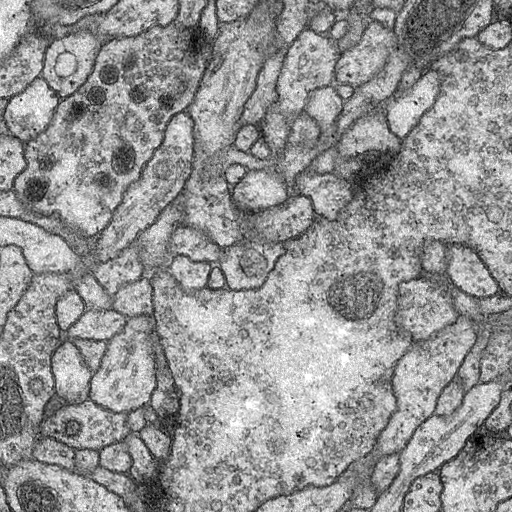

The images are 3-D volume tiff, you should transfer the stacks into images first. The data for training contains 30 512*512 images, which are far not enough to feed a deep learning neural network. To do data augumentation, an image deformation method was used, which was implemented in C++ using opencv.

Output from the network is a 512*512 which represents mask that should be learned. Sigmoid activation function makes sure that mask pixels are in [0, 1] range.

First transfer 3D volume tiff to 30 512*512 images.

Use the trained model to do segmentation on test images, the result is statisfactory.